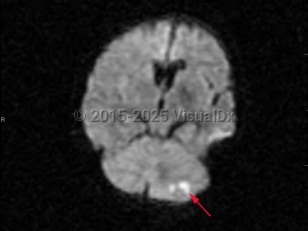

- Ischemic cerebellar strokes are predominantly either thrombotic or embolic. Thrombotic strokes are often caused by atherosclerosis, while embolic strokes are commonly cardiogenic (atrial fibrillation), septic, or due to coagulopathy.

- Hemorrhagic strokes can be intraparenchymal, due to hypertension, or secondary to subdural or subarachnoid hemorrhage.

Risk factors for cerebellar strokes are the same as for other cerebrovascular pathologies: hypertension, hyperlipidemia, diabetes, cardioembolic risks such as atrial fibrillation, and tobacco abuse are chief among them. Cerebellar hemorrhages can also be caused by a rupture of vascular malformations; hereditary hemorrhagic telangiectasia (HHT) is a particular risk factor. Rupture of vascular malformations is a more likely cause in children. Other risk factors for cerebellar hemorrhages include sympathomimetic abuse such as cocaine use. Increased urinary sodium is associated with increased risk.